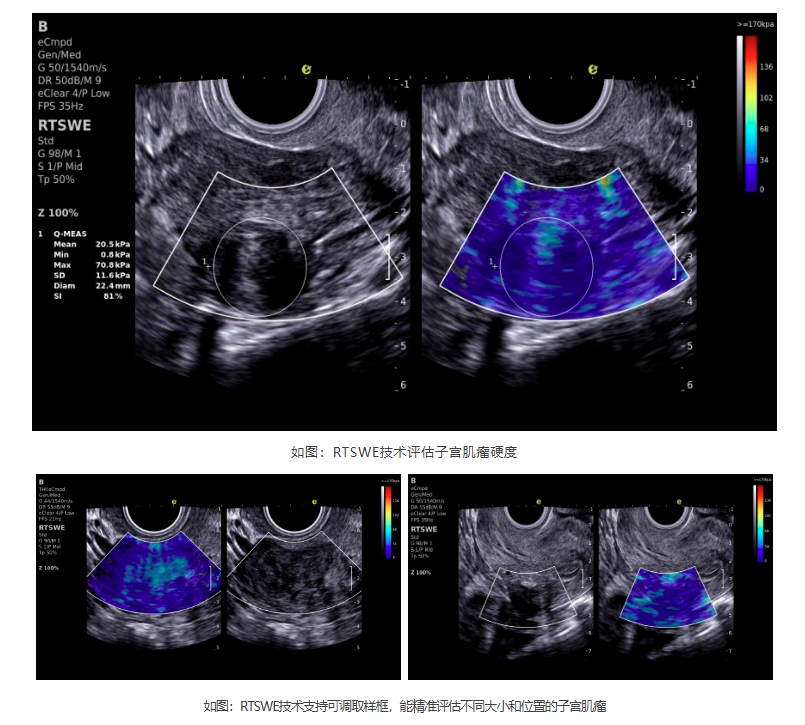

如今,3377体育医疗ePascal东风系列搭载的RTSWE?实时E成像技术为肌瘤良恶性的鉴别带来了突破!该技术基于OmniSound? 平面波超快速平台,以25000帧/秒的采集帧频,实现最小0.4mm病灶的精准硬度测量。它犹如为超声检查赋予"智能触诊"能力,通过定量分析组织硬度,辅助判断肌瘤性质:

良性肌瘤:质地均匀,硬度较高(类似橡皮)

恶性肉瘤:硬度不均,整体更坚硬(类似石头)

变性肌瘤:如红色变性时,硬度会相应降低

RTSWE?技术优势

? 安全无创——零辐射、无痛苦,检查更舒适

? 减少过度检查——降低不必要活检

? 生育友好——专为备孕女性定制肌瘤评估方案

? 动态监测风险——敏感捕捉绝经后肌瘤的异常

? 指导精准治疗——为手术决策提供客观依据

cd2301cd65513af0501835669682402.png

潜伏在子宫里的"小石头",看似无害,却需要及时关注。3377体育医疗RTSWE?实时E成像技术以毫米级精度实现子宫肌瘤可视化诊断,突破性探测病灶质地特性,为临床决策提供新维度。该技术助力女性通过精准超声检测,获得更安心的健康保障。